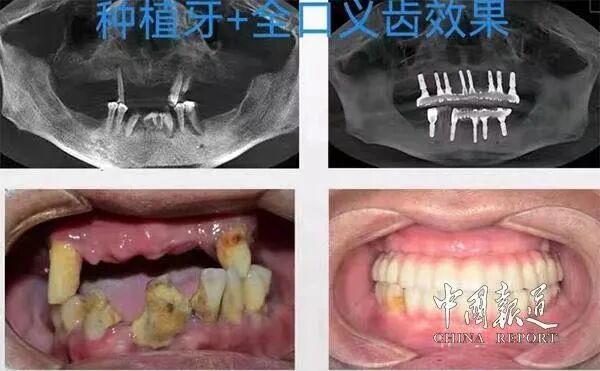

(种植牙效果)

种植几乎适用于所有缺失牙,相比于烤瓷牙、活动义齿具有无伤害—不磨损健康邻齿、强功能—咀嚼如真牙、更美观—颜色比真牙、使用年限长等优势,是现代口腔修复的最佳选择。种植牙以其稳固、耐用、好用的优点被口腔医学界公认为缺牙修复的优选方式,也被称为“人类的第三副牙齿”。